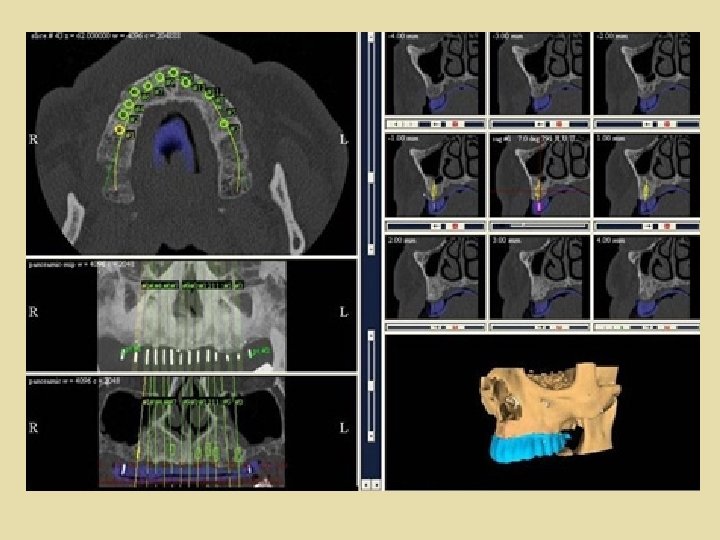

TAC Hay autores que plantean que la utilización racional de férulas sólo puede utilizarse con TAC. Para poder interpretar los hallazgos obtenidos con TAC es necesario realizarla con una férula radiológica construida con un material radiopaco que representa la posición correcta de la futura prótesis que va ser soportada por implantes, así podemos valorar la posición y angulación de los futuros implantes, según el hallazgo de TAC.

TAC Con la tomografía axial computarizada, disponemos de la posibilidad de realizar reconstrucciones secciónales y tridimensionales en los maxilares, y convertir en realidad el deseo del implantólogo de conocer con absoluta precisión las características dimensionales y la densitometría del área exacta a implantar. Ello puede también obtenerse con

TAC Aplicando un determinado software a la interpretación de los datos obtenidos en la tomografía convencional y se consigue un detallado estudio sectorial tridimensional y panorámico de los huesos maxilares, esencial para el diagnóstico y planificación de estudios en los sectores críticos, sectores posteriores de la mandíbula y maxilar superior.